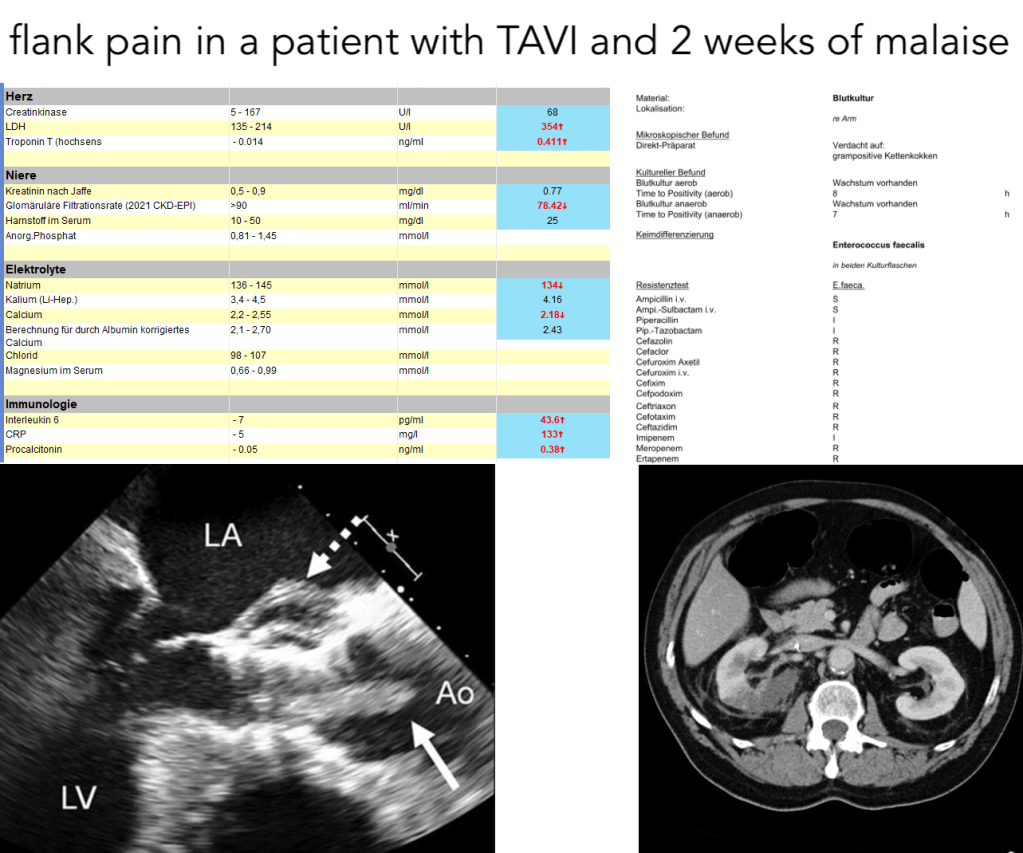

flank pain